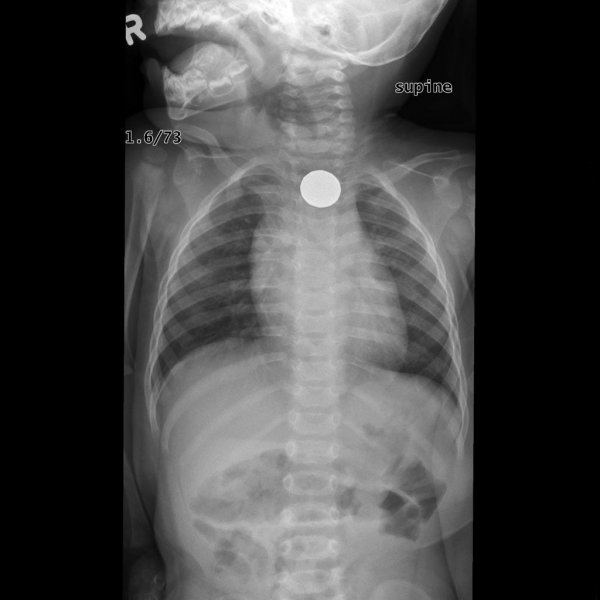

Специалисты по рентгеновской диагностике регулярно сталкиваются с посторонними предметами внутри тела человека. Обычно лишние предметы попадают в пищеварительную систему из-за неосторожности при еде или во время неудачных любовных игр. Почти всё удается вытащить — с хирургическим вмешательством или без него. выбрал самые необычные находки радиологов, которыми они делились на сайте Radiopaedia.org.